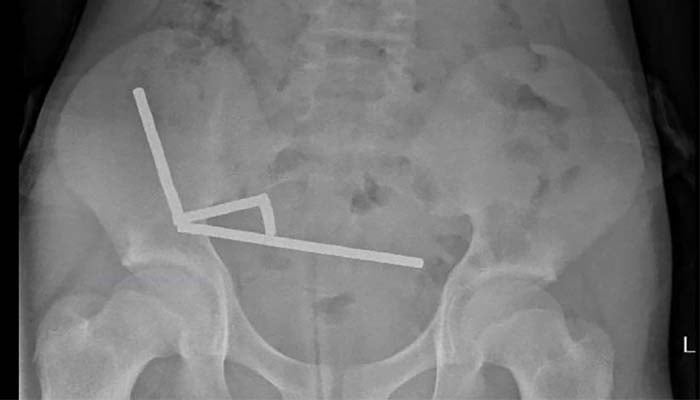

An X-ray revealed dozens of tiny neodymium magnets — banned in New Zealand since 2013 clustered together inside his intestines, impeding blood supply and causing necrosis in the four areas of the boy's small bowel and caecum.